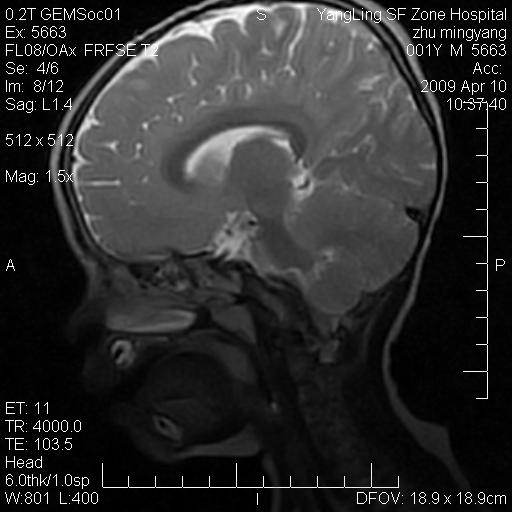

患者:1岁半,两天前外伤收住我院,ct检查小脑占位

考虑星形细胞瘤,建议增强

髓母细胞瘤或血管母细胞瘤,增强后可以鉴别;影像资料见 <。鱼博浪老师的《中枢神经系统ct与mr鉴别诊断》 小脑部肿瘤章节。

髓母细胞瘤或血管母细胞瘤!支持!

支持考虑髓母细胞瘤

考虑----髓母细胞瘤可能性大

考虑髓母细胞瘤或室管膜瘤。

支持髓母细胞瘤。

考虑髓母细胞瘤。

考虑髓母细胞瘤或星形细胞瘤

考虑髓母细胞瘤.

考虑髓母细胞瘤可能性大。

小脑肿瘤.考虑髓母细胞瘤可能.

就病灶部位及临床资料首先考虑髓母.